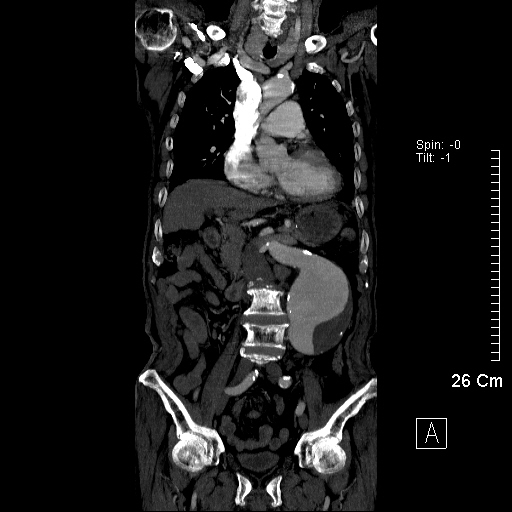

現在的我們,可以透過電腦斷層影像的重組,更方便的見到這些個讓生命得以運行的通道。圖片裡呈現的便是主動脈,也正是體內重要的縱貫線。

老化的主動脈,還可能出現主動脈剝離。這張圖裡的主動脈,可以明顯見到多出了隔間。這種以劇烈疼痛來表現的急症,有時會相當棘手。